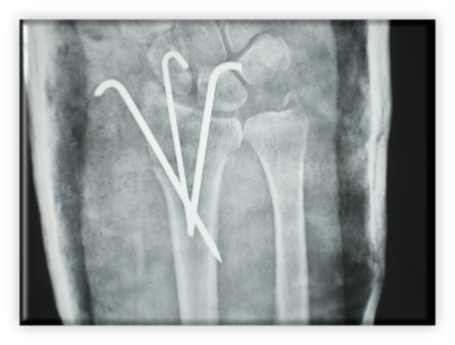

Πρόκειται όμως για ασταθή κατάγματα και παρά την ικανοποιητική ανάταξη και γύψωση, μερικές φορές το κάταγμα παρεκτοπίζεται στο γύψο. Η τελική αντιμετώπιση ήταν η σταθεροποίηση με βελόνες Κirschner, μια ανέξοδη και πολύ αποτελεσματική μέθοδος. Ο συνολικός χρόνος ακινητοποίησης είναι 6 εβδομάδες και συνήθως ακολουθεί περίοδος φυσικοθεραπείας. Μετά από ένα τέτοιο κάταγμα σε μια μετεμμηνοπαυσιακή γυναίκα, εξέχουσας σημασίας είναι ο έλεγχος και θεραπεία οστεοπόρωσης.

Μέθοδος εκλογής από την πλευρά μου είναι η οστεοσύνθεση με ενδοαυλική βελόνα Kirschner.

Πρόκειται για μέθοδο ελάχιστης παρεμβατικότητας αφού το κάταγμα ανατάσσεται κλειστά και η είσοδος της βελόνας γίνεται από μία μικρή τομή στη βάση του 5ου μετακαρπίου.

Με την είσοδό της η βελόνα συμβάλει στην ανάταξη του κατάγματος όπως φυσικά και στη συγκράτησή του.

Παράλληλα επιτυγχάνεται και η αποκατάσταση του μήκους του οστού.

Στη συνέχεια δεν χρησιμοποιείται νάρθηκας και η κινητοποίηση του δακτύλου είναι άμεση.

Η βελόνα αφαιρείται στο εξωτερικό ιατρείο χωρίς την ανάγκη αναισθησίας.